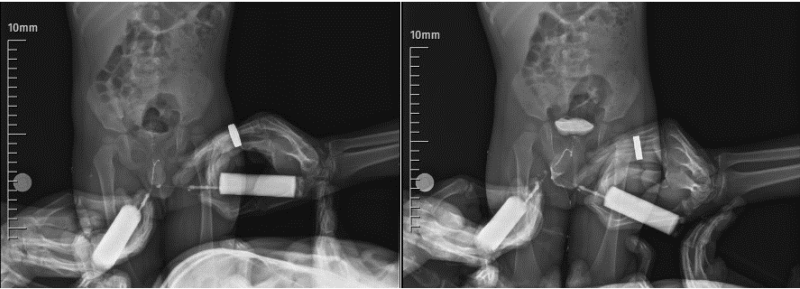

Diphallus, which is also known as diphallia, is a very rare congenital anomaly encountered nearly one in 5.5 million population. Since the first case was presented by Wecker in 1609, only 120 cases have been reported in the literature so far. Vast majority of cases with diphallus were accompanied by various congenital anomalies mainly genitourinary and anorectal malformations. Diphallus can be classified as glandular diphallus, bifid diphallus, and complete diphallia according to the anatomical structure involved.